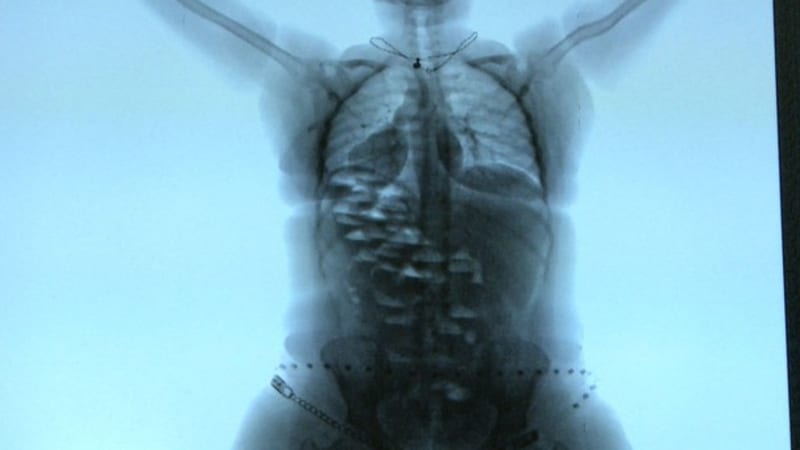

“We Are Not Done Yet” is a creative journey of ten U.S. veterans of varied backgrounds who come together in hopes of battling their traumatic military pasts through the art of written word. Grappling with PTSD, the “warrior poets” share fears, vulnerabilities, and victories that, eventually culminate into a live performance of a collaborative poem under the direction of actor Jeffrey Wright. In the process of creating their poetry and rehearsing for the performance, these men and women build a new-found tribe in one another, allowing them to share the too often hidden truths about their intimacy with war, death, and trauma.